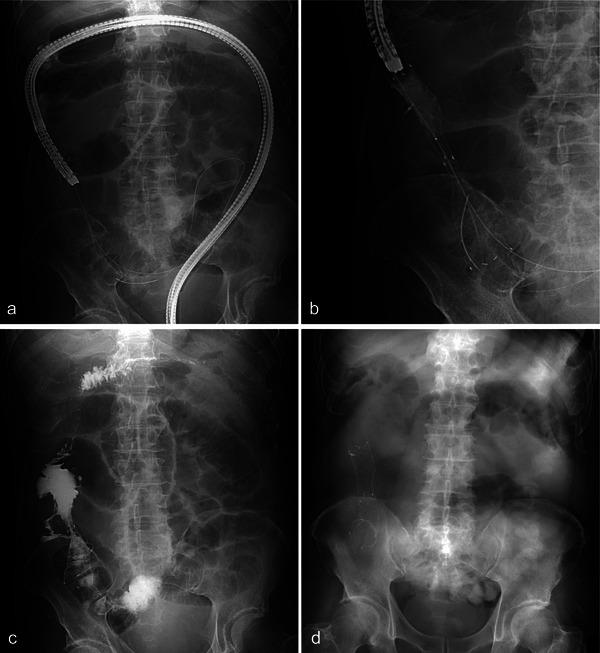

Self-expanding metallic stents (SEMSs) are an established palliative option for malignant colonic obstruction, including in cases with proximal lesions. However, SEMS placement across the ileocecal valve (ICV) can be technically challenging because of the anatomical curvature and luminal stenosis. Herein, we report a successful case of colonic stenting for a malignant ileocecal obstruction using an ultra-thin scope and a single-balloon overtube. A 72-year-old man with alcoholic cirrhosis and multiple liver metastases presented with malignant ileocecal obstruction. Given his inoperability, palliative SEMS placement was attempted. Colonoscopy showed a circumferential tumor in the ileocecum, with no passage of contrast medium into the ileum. Guidewire insertion across the ICV failed because of the inability to visualize the direction of the ileal lumen. To overcome this, we used a rescue technique with an ultra-thin scope and a single-balloon overtube. After placing the overtube in the ascending colon, the ultra-thin scope was advanced through it to explore the stenotic lumen directly. This allowed safe insertion of the guidewire into the proximal lumen of the stenosis. The ultra-thin scope was withdrawn, and a standard scope was inserted over the guidewire. Finally, a SEMS was deployed across the ICV through the scope. The patient's obstructive symptoms were resolved without complications, and he was discharged 7 days later. This case demonstrates that in cases of malignant ileocecal obstruction where SEMS placement using conventional methods is difficult, a rescue technique using an ultra-thin scope with a single-balloon overtube may be a viable alternative.

自膨式金属支架(SEMSs)是治疗恶性结肠梗阻的一种成熟的姑息治疗选择,包括近端病变的病例。然而,由于解剖学弯曲和管腔狭窄,将SEMS放置在回盲瓣(ICV)处技术上具有挑战性。在此,我们报告一例使用超薄内镜和单球囊外套管成功治疗恶性回盲部梗阻的结肠支架置入病例。一名72岁患有酒精性肝硬化和多处肝转移的男性患者出现恶性回盲部梗阻。鉴于其无法手术,尝试进行姑息性SEMS置入。结肠镜检查显示回盲部有一环形肿瘤,造影剂无法进入回肠。由于无法看清回肠腔的方向,穿过ICV插入导丝失败。为克服这一问题,我们采用了一种使用超薄内镜和单球囊外套管的挽救技术。将外套管置于升结肠后,将超薄内镜通过它推进以直接探查狭窄管腔。这使得导丝能够安全地插入狭窄近端管腔。拔出超薄内镜,在导丝上插入标准内镜。最后,通过内镜在ICV处释放一枚SEMS。患者的梗阻症状得以缓解,无并发症发生,7天后出院。该病例表明,在使用传统方法放置SEMS困难的恶性回盲部梗阻病例中,使用带有单球囊外套管的超薄内镜的挽救技术可能是一种可行的替代方法。